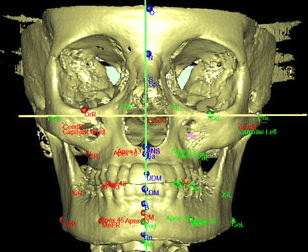

• Cefalometria 3D